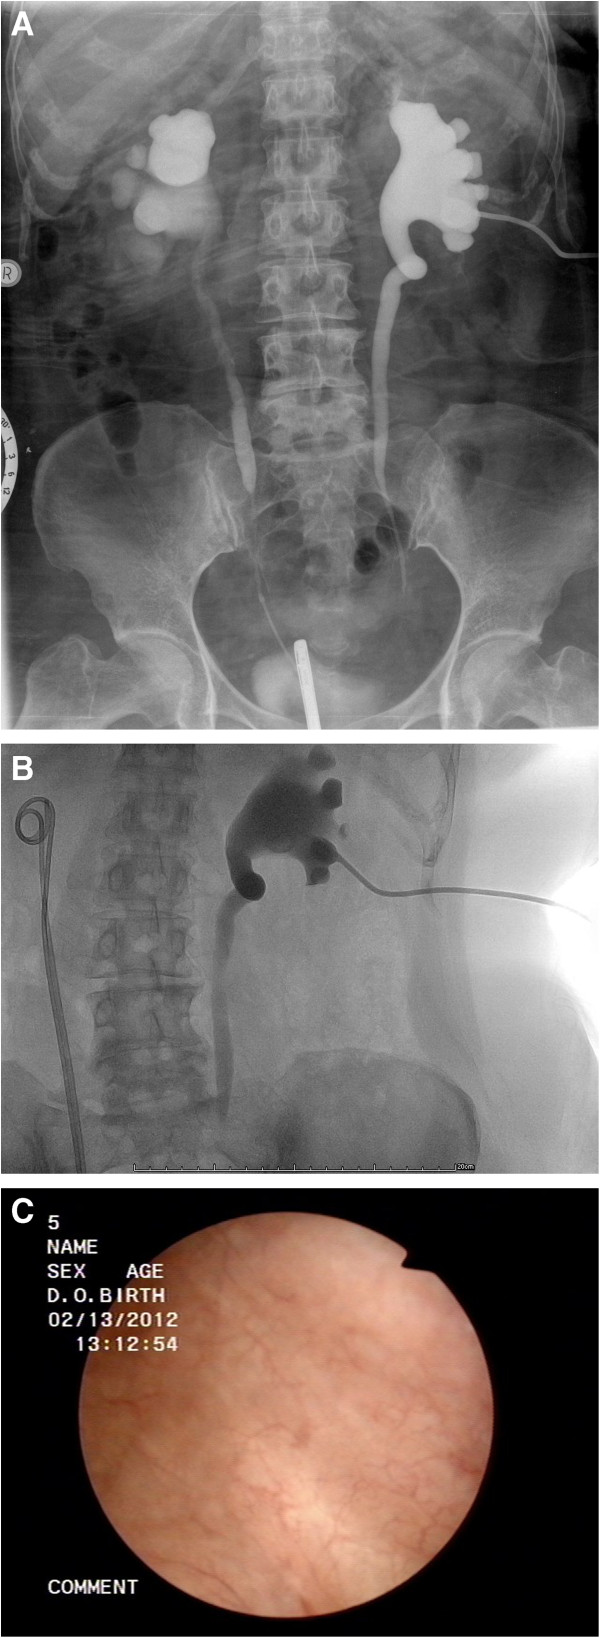

Post radiotherapy treatment I . V . Pyelography . Bilateral Ureteral Stenosis and Hydronephrosis (Courtesy Dr. V. Penopoulos)